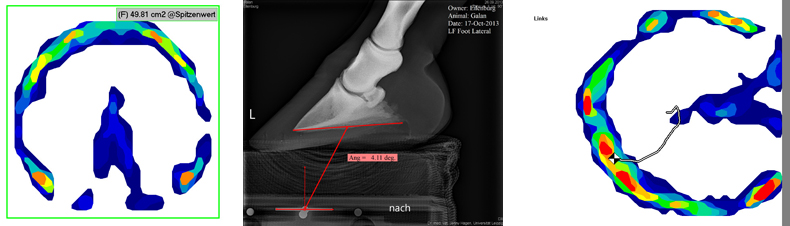

A vizsgálatban szereplő 70 lovat (mindegyik patkó nélküli, napi 4 – 8 órát tölt a legelőn, hasonló takarmányozási és használati körülmények között tartott állat) a három csoportra osztották és 10 hónapon keresztül követték nyomon. 8 hetente, mindegyik körmölés előtt és után morphometriai és kinetikus méréseket végeztek, valamint az első és utolsó körmölésnél röntgenfelvételek készültek.

A morphológiai vizsgálatok a várakozásoknak megfelelően határozott korrelációt mutattak a párta- és hordozószél kerülete, a külső és belső saroktámasztó, a külső és belső sarokfal, valamint a pata és a nyír hossza között. Ésszerű támpontnak tűnik a gyakorlat számára a nyír hegyének felkeresése és a pata ehhez viszonyított igazítása.

A hegy- és sarokfal hosszának 3:1-ben ill. 2:1-ben meghatározott arányát (az elülső ill. hátulsó pata esetében) inkább ideális értéknek tekinthetjük csupán, de nem találtak szoros összefüggést a két érték között. Lényegesen fontosabb paraméternek mutatkozott a sarokfal szögellése, semmint annak hossza, hiszen ez utóbbi nem igazodott a pata talajjal bezárt szögéhez.

Radiológiai vizsgálatok igazolták, hogy a párta- és csüdcsont egymáshoz viszonyított pozíciója sokkal szorosabb összefüggést mutat, semmint az ő patacsonthoz képest kialakult helyzetük. A patacsont szorosan rögzül a szarutokban és a pártacsonttal (+ nyírcsonttal) alkotott összetett pataízület jelentős mozgásszabadsága biztosítja a többé-kevésbé fennálló függetlenségét, míg a pártaízület a csüdcsont felé egy igen feszes kapcsolatot hoz létre. Következésképpen a pataízület szimmetriáját nemigen befolyásolja a patacsont mediolateralis pozíciója, míg a párta- és csüdcsont helyzete jelentős hatással bír erre a paraméterre. Ebből adódóan kérdéses, hogy a pataízület szimmetriáját sikerül-e a patacsont mediolateralis szögellés-változtatásával optimalizálnunk.

A szarutok oldalfalának a talajjal bezárt szöge függetlennek mutatkozott egyrészt a patacsont helyzetétől, másrészt a pataízület szimmetriájától. A dorsopalmaris felvételen általában mintegy 2°-os mediális ill. laterális dőlés volt látható, míg a 90°-os felvételen a patacsont talajjal bezárt szöge átlagosan 5,2°volt. (A 70 lóból ezen érték három esetében volt negatív és három esetben >13°.)

Kinetikus vizsgálatok tanúsága szerint a terhelés mintegy 60%-a a szarutok elülső részére esik, míg a teherviselés középpontja kb. 1 cm a pata közepe előtt, azaz a nyírhegynél volt. Lépésben és álló helyzetben a terhelés dorsopalmáris megoszlása és a teherviselés középpontja igen szoros összefüggést mutatott. A terhelés mediolateralis megoszlása azonban lépésben és álló helyzetben jelentősen eltért. Míg álló helyzetben ez az érték igen kiegyensúlyozott volt (53% a pata belső oldalán), addig lépésben 57% a külső oldalon volt. A teherviselés középpontját a pata állásán túl a ló felépítése jelentősen befolyásolja és a ló alkatát körmöléssel nem tudjuk módosítani.

Nem találtak összefüggést a pata-, párta-, csüdcsont mediolaterális pozíciója és a terhelési középpont mediolaterális helyzete között. Ebből adódóan nem feltételezhető, hogy az egyenes ujjtengely a pata egyenletes terhelését eredményezi. Az ízületi résekre kifejtett hatás nehezen ismerhető fel.

Az oldalfalak szögelléséről elmondható, hogy sokszor a meredekebb nagyobb terhelésnek van kitéve, azonban mediolaterálisan jelentősen eltérő patájú lovaknál is sokszor egyenletesen megoszló és központra fókuszáló teherviselést regisztráltak – és fordítva.

A talajfogást vizsgálva megállapítható, hogy a legtöbb ló patája (25 a jobb, míg 31 a bal lábon) laposan, egyenletesen, de csaknem ugyanennyi (30 ill. 23 ló) a pata külső oldalára érkezett. 11 – 11 ló a pata hegyével fogott talajt, míg az oly’ gyakran megcélzott sarokfali érkezés csupán 2 ill. 3 ló esetében mutatkozott. Nem találtak összefüggést a lapos talajfogás és a teherviselés középpontja között: kifejezett billenést mutató lovak esetében is gyakran teljesen centrálisan helyeződött a terhelés.